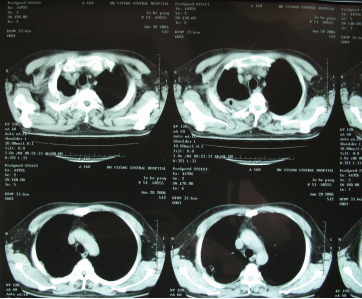

手術(shù)后CT顯示

回家之后,魯叔遵從醫(yī)囑,1月21日便去當(dāng)?shù)蒯t(yī)院復(fù)查,CT顯示腫瘤從原來的10×10cm縮小到2.6×1.3cm?!澳莻€醫(yī)生很吃驚,以為機器故障,又為我免費做了一次檢查。”更讓人感到吃驚的是,術(shù)后三個月他的腫瘤完全消失。事實上,腫瘤的完全消失不僅僅是治療起作用,術(shù)后的康復(fù)也很關(guān)鍵。魯叔從熬夜抽煙喝酒到后來戒煙戒酒生活作息規(guī)律,心態(tài)保持著樂觀,并堅持上班不斷充實自己,以最好的狀態(tài)面對每一次復(fù)查,直到2020年7月,他的身上依舊無任何腫瘤復(fù)發(fā)跡象?!皬?4年的時候我每天都在計算,算著自己還有多少天,但是我現(xiàn)在已經(jīng)從100天活到了第60個100天?!?/p>